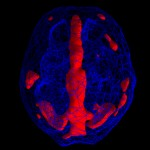

Brain map tega podtipa pokaže povišano aktivnost v stanju relaksacije, kot pri koncentraciji v predelu cingulate gyrus, ter zmanjšano aktivnost v prefrontalnem korteksu, bazalnih ganglijih in cerebellumu.

Brain map običajno pokaže povišano aktivnost v limbičnem predelu, med počitkom in koncentracijo. V limbičnem predelu se generirajo čustva, kontrolira se kako smo srečni ali nesrečni. Depresija je tesno povezana z limbičnim predelom. Zmanjšana je aktivnost v prefrontalnem predelu, v cerebellumu in bazalnih ganglijih.